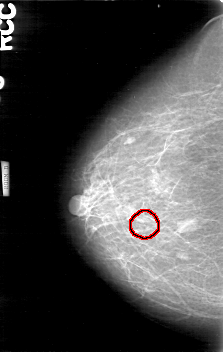

D_4170_1.RIGHT_CC

RIGHT_CC LINES 5266 PIXELS_PER_LINE 3331 BITS_PER_PIXEL 12 RESOLUTION 43.5 OVERLAY

FILE: D_4170_1.RIGHT_CC.OVERLAY

TOTAL_ABNORMALITIES 1

ABNORMALITY 1

LESION_TYPE CALCIFICATION TYPE AMORPHOUS DISTRIBUTION CLUSTERED

ASSESSMENT 0

SUBTLETY 2

PATHOLOGY BENIGN

TOTAL_OUTLINES 1